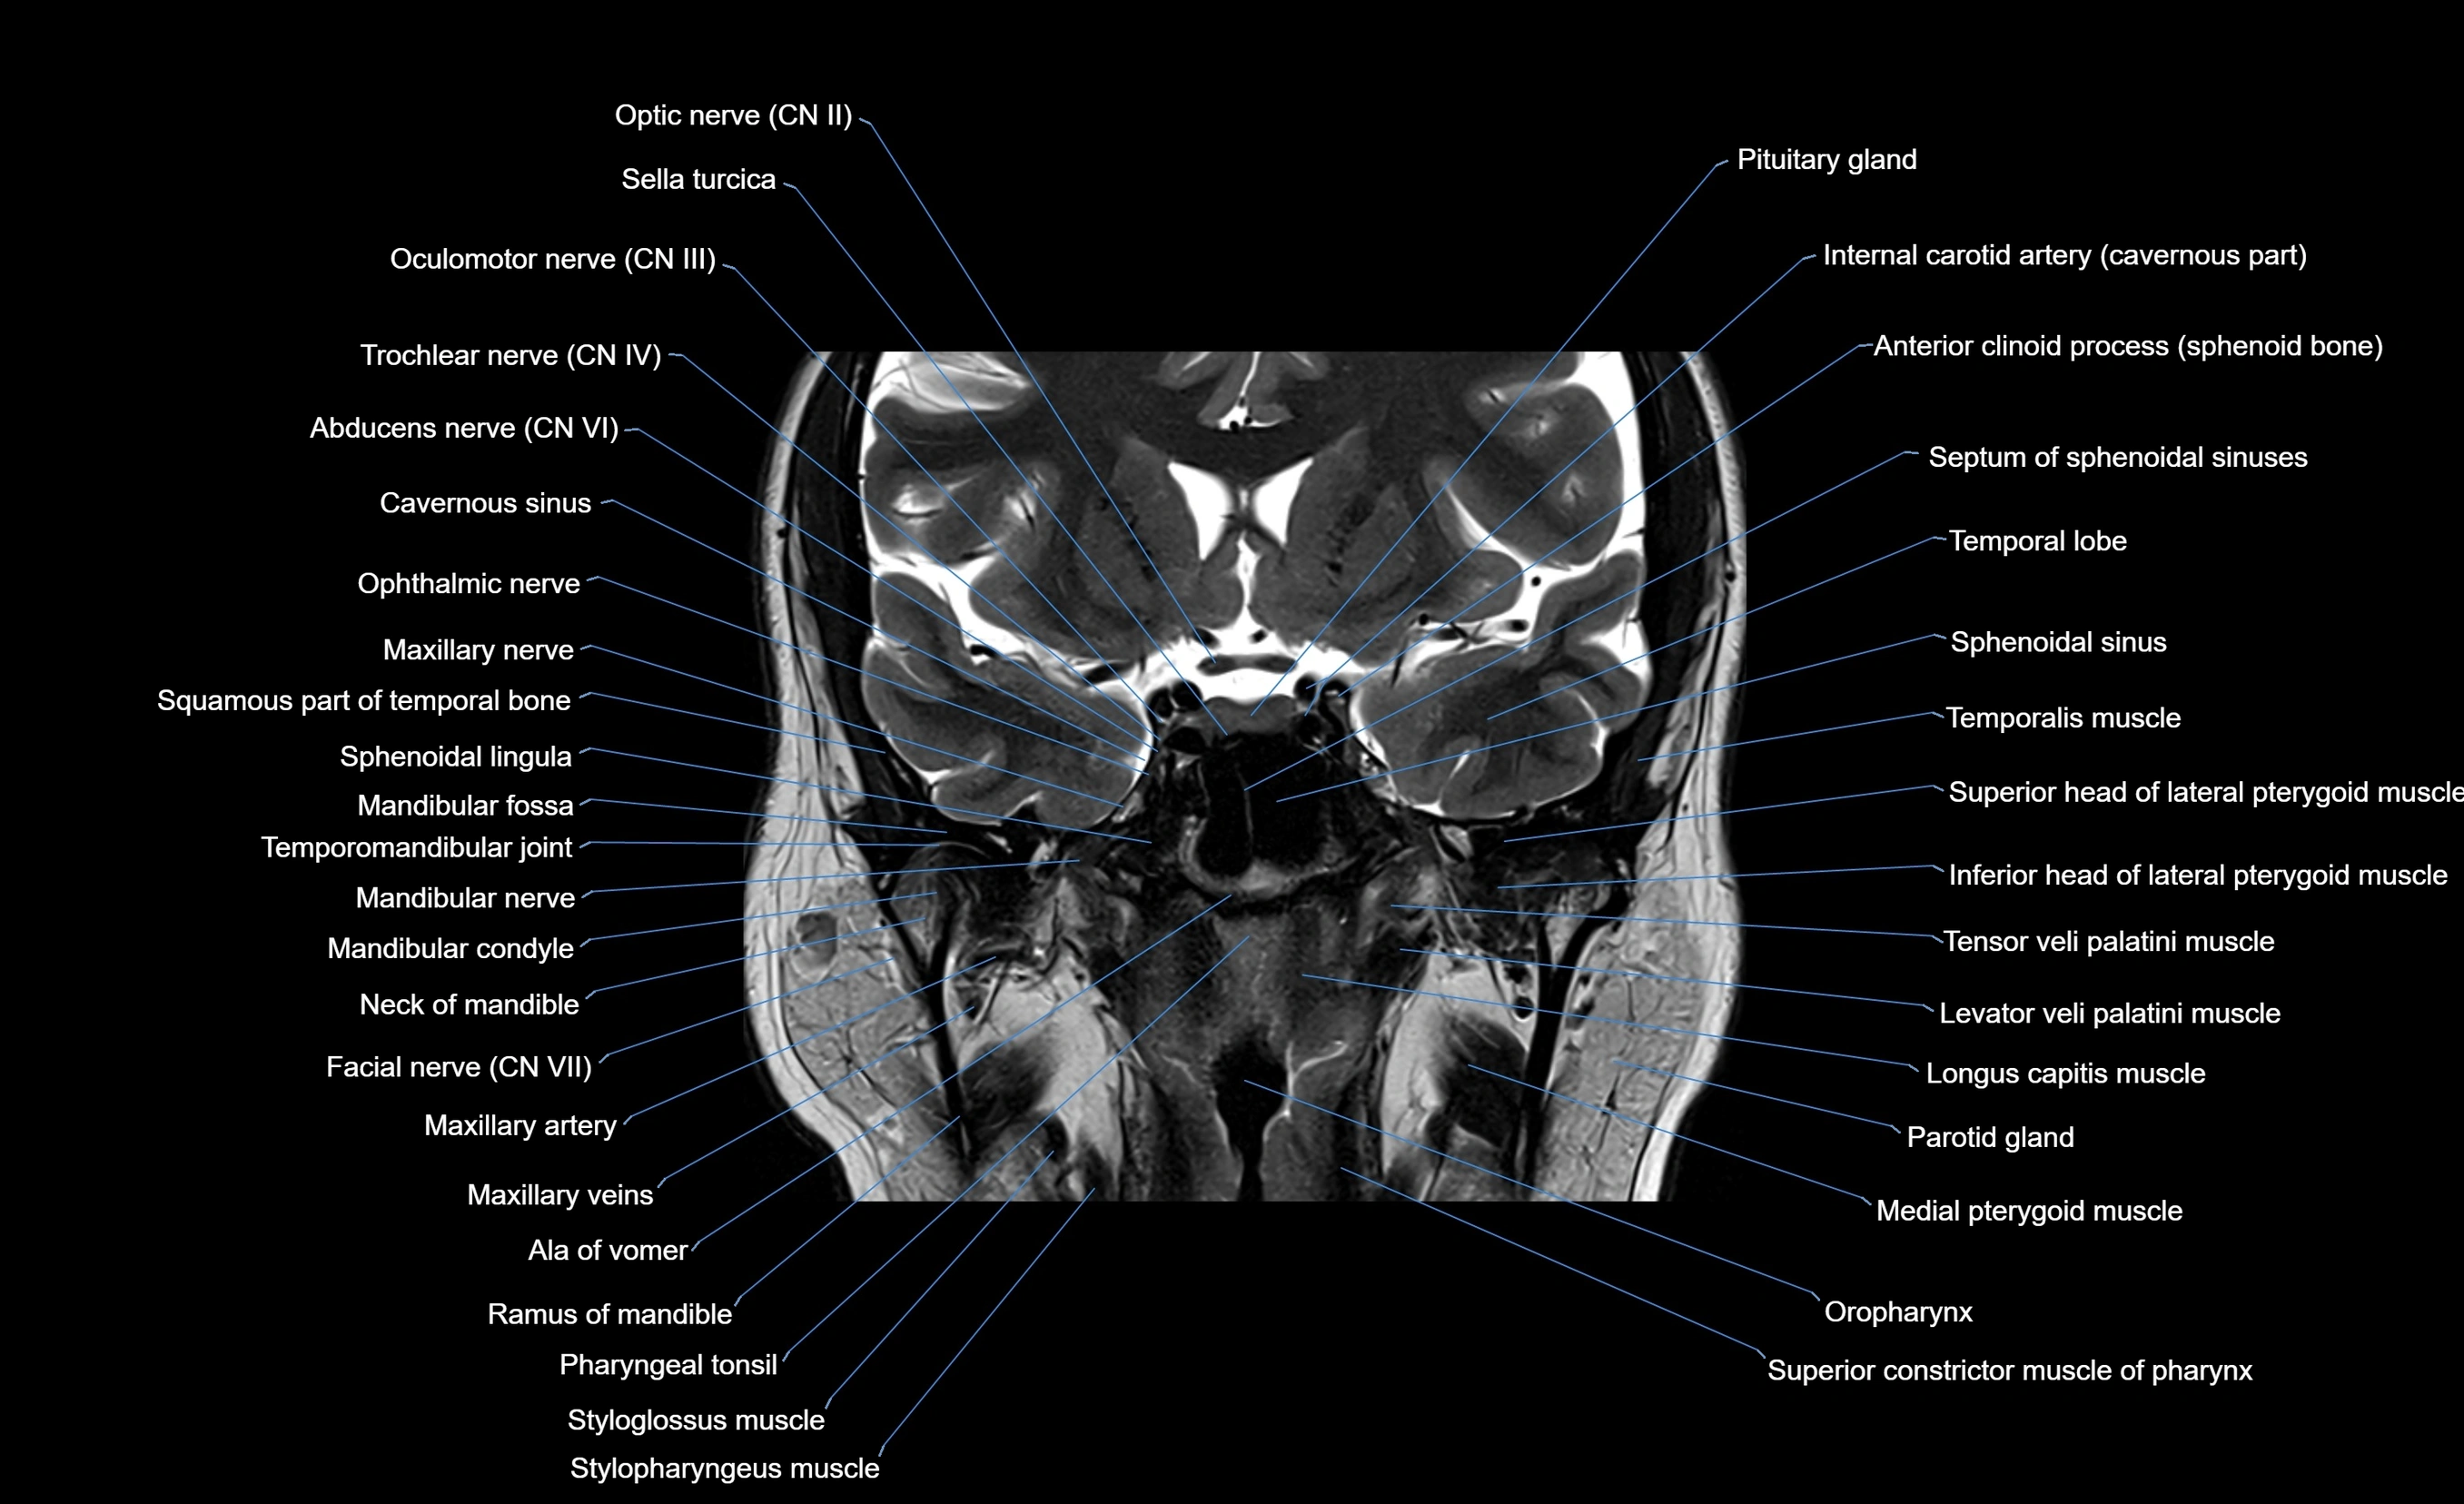

MRI images